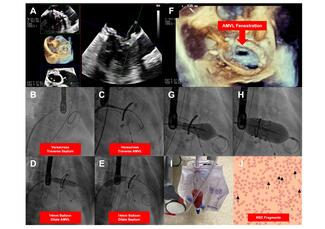

The authors introduce a simplified BATMAN workflow using a VersaCross and a 14-mm balloon for both septum and A2 fenestration, and outline an approach to post-transcatheter mitral valve replacement hemolysis.